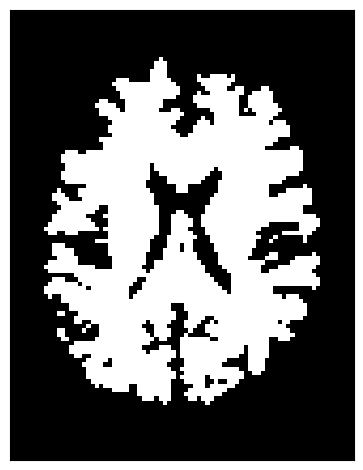

2️⃣ Binary Stopping Criterion

Instead of stopping based on a continuous scalar map (like FA), the binary criterion relies solely on a white matter mask. Tracking is allowed only inside the mask—as soon as the current position lies outside it, the streamline terminates.

This criterion uses nearest-neighbor interpolation to determine whether the current tracking location is inside (mask = 1) or outside (mask = 0) the white matter.

stopping_criterion_binary = BinaryStoppingCriterion(white_matter)

plt.imshow(white_matter[:, :, data.shape[2] // 2].T, cmap='gray',

origin='lower', interpolation='nearest')

<matplotlib.image.AxesImage at 0x7f225dc05810>

../../_images/d58ecb80264497373b92f24cdcc3faefa8ecc9396f7989f75215c9edfc33b7ae.png

This approach is simpler and ensures that streamlines remain strictly within the white matter mask.